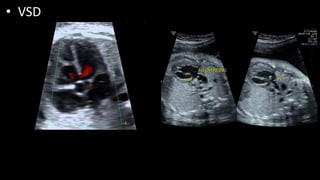

• VSD

• Echocardiography

Two-dimensional echocardiography and Doppler studies usually make the

diagnosis and quantitate the severity of TOF.

1. A large, perimembranous infundibular VSD and overriding of the aorta are

readily imaged in the parasternal long-axis view (Fig. 14-20).

•

2. Anatomy of the RVOT, the pulmonary valve, the pulmonary annulus, and

the main PA and its branches is imaged in the parasternal short-axis and

subcostal short-axis views. These views allow systematic evaluation of the

severity of obstruction at different levels.

3. Doppler studies estimate the pressure gradient across the RVOT

obstruction.